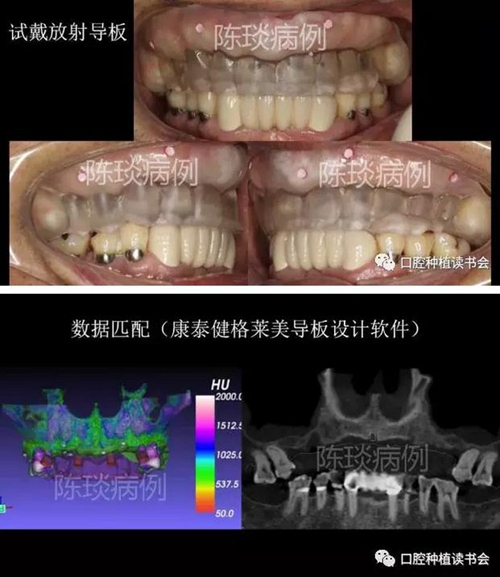

(1)制作臨時義齒以及放射導板,根據石膏模型設計放射導板,并確定顯影標記。

3.jpg

(2)佩戴放射導板拍CBCT后,設計數字種植導板。

4.jpg

5.jpg

6.jpg

7.jpg